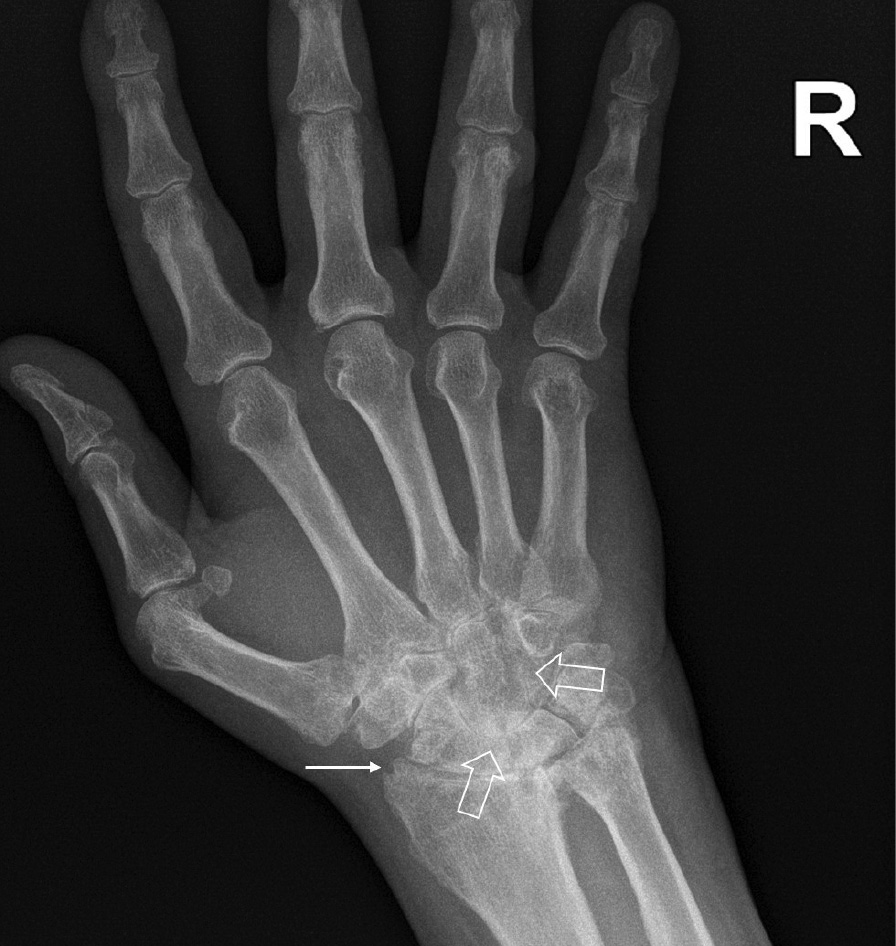

При компьютерной томографии органов грудной клетки данных за «свежие» очаговые и инфильтративные изменения не получено. Увеличения лимфатических узлов подмышечных областей, средостения, корней легких не выявлено. Отмечался усиленный грудной кифоз, обызвествление передней продольной связки, на всем уровне исследования определялись передне-боковые спондилофиты, а также анкилоз большинства реберно-поперечных суставов. По данным рентгенографии кистей (рис. 1, 2) и стоп (рис. 3, 4) диагностированы признаки эрозивного артрита, анкилоз суставов запястья. По данным МРТ крестцово-подвздошных суставов (КПС) определялся неравномерный анкилоз КПС, хрящи по суставным поверхностям неравномерной толщины, примерно на половине протяжении сустава отсутствуют, «суставной промежуток» облитерирован. Неравномерность и нечеткость контура суставных поверхностей за счет множества краевых эрозий справа, единичных – слева, с наличием остеокластоза, в нижнем отделе слева по смежным отделам определяются участки трабекулярного отека, данная находка клинически интерпретирована как двусторонний активный сакроилиит (рис. 5, 6).

Рис. 2. Рентгенограмма правой кисти в прямой проекции. Краевая эрозия суставной поверхности лучевой кости (тонкая стрелка), множественные анкилозы суставов запястья (толстые стрелки)

В возрасте 40 лет присоединились жалобы на симметричные воспалительные боли в лучезапястных суставах и мелких суставах кистей, резкое снижение объема движения в лучезапястных суставах. При осмотре пациента выявлено: число болезненных суставов – 7, число припухших суставов – 4, положительный симптом поперечного сжатия кистей и стоп, ульнарная девиация мелких суставов стоп. Резко сниженный объем движения в лучезапястных суставах обеих кистей. По данным рентгенологического обследования зафиксированы типичные изменения для РА: резкое неравномерное выраженное сужение суставных щелей, субхондральный склероз в лучезапястных суставах, анкилоз в суставах запястья, пястно-запястных, пястно-фаланговых и межфаланговых суставах. Краевые эрозии оснований основных фаланг двух пальцев; участки кистовидной перестройки костной ткани. Локальное утолщение мягких тканей. При лабораторном обследовании пациента отмечен положительный ревматоидный фактор, высокий титр антицитруллинированных антител, повышение острофазовых белков.